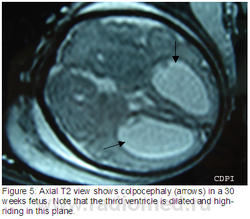

5. На акс. Т2 колпоцефалия у 30 недельного плода. Обратите внимание, что 3 желудочек расширен и расположен высоко.